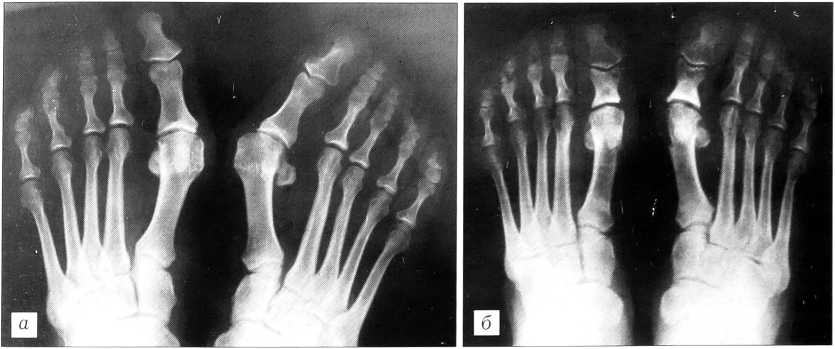

Пример. Больная К., 39 лет, находилась в клинике ЦИТО с диагнозом: двустороннее поперечное плоскостопие, hallux valgus III степени. 27.01.71 произведена реконструктивная операция по методике ЦИТО на обеих стопах. Отдаленный исход через 12 лет расценен как хороший: исправленная форма переднего отдела стоп сохраняется, движения в I плюснефаланговом суставе в полном объеме, безболезненные; ходит в обычной обуви (рис. 2).

Рис. 2. Рентгенограммы стоп больной К.а — до операции; б — после оперативного лечения.